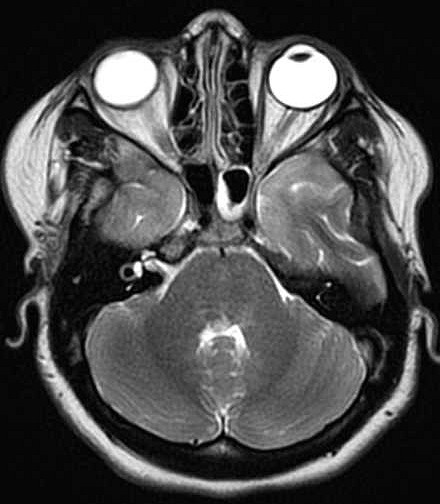

| Fem. 17a. |

| Nódulo sólido homogêneo preenchendo o III ventrículo, com limites precisos, com hipossinal em T1 e hipersinal em T2 e FLAIR, que se impregna por contraste paramagnético. Lesão menor implantada no assoalho do IV ventrículo provavelmente representa disseminação por via liquórica. |

| F. 17a. Tumor teratóide rabdóide atípico de III ventrículo. RM | HE | VIM, GFAP | HHF35, desmina, 1A4 | AE1AE3, EMA |